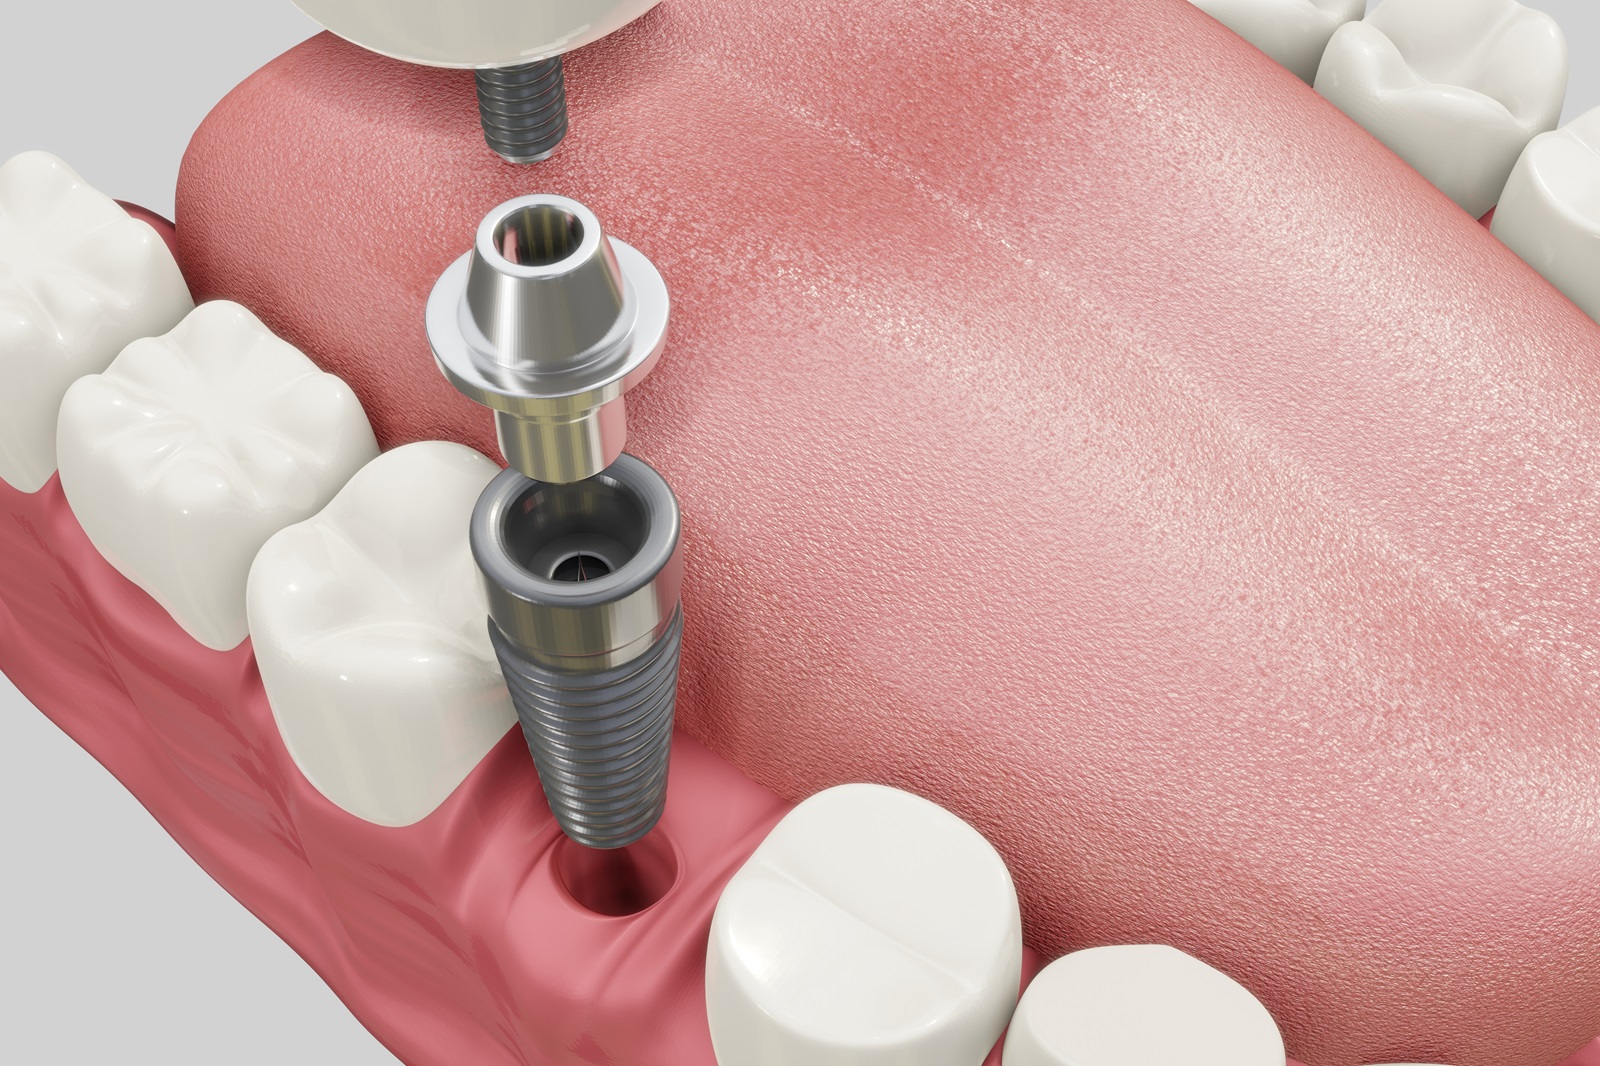

ケース3ブリッジやインプラントがある

インプラントは顎の骨にしっかりと結合されているため、矯正治療で動かすことはできません。矯正治療では歯全体を移動させて歯列を整える必要がありますが、インプラントが固定されたままだと、その周囲の歯の移動が制限される可能性があります。この制限により、理想的な歯並びや噛み合わせを実現するための治療計画に影響を及ぼす場合があります。

「インプラント」などがある場合

一部の歯が欠損している場合や、インプラントブリッジなどの補綴物が装着されている場合には、治療計画を慎重かつ詳細に立案することが重要です。具体的には、天然歯をどの程度移動させるのか、欠損部位をどのような補綴物で補うのかといった点を、矯正治療だけでなく補綴治療も含めて総合的に検討する必要があります。

当院では、矯正治療と補綴治療の両面からアプローチすることで、患者さんのお口の状態に最適な治療を行っています。